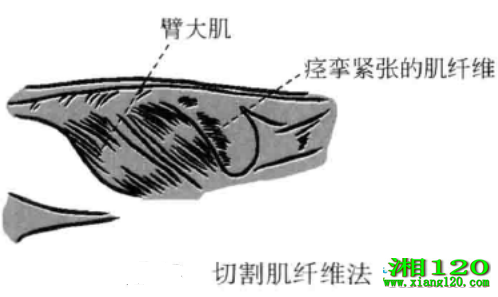

8、切割肌纤维法

当某处因为部分肌纤维紧张或痉挛,引起顽固性疼痛或功能障碍时,将刀口线沿肌纤维垂直刺入,切断少量紧张或痉挛的肌纤维,往往可使得症状立即减轻。